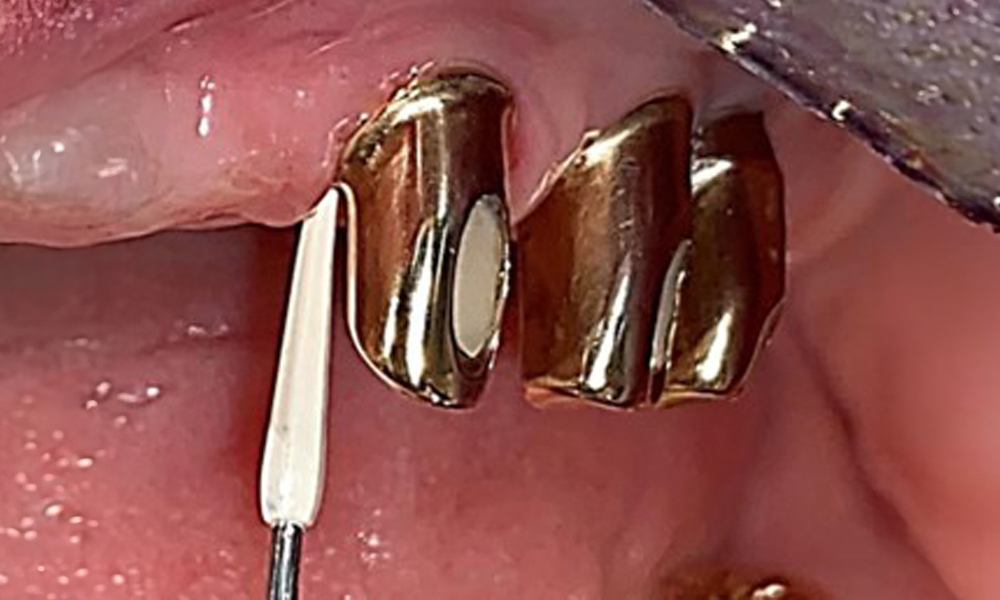

The patient was fitted with a combined removable maxillary telescopic prosthesis more than 25 years ago (Fig. 1, Fig. 2, Fig. 3) and is very happy with her dentures. The patient has an adequate fixed denture for the mandible (Fig. 4).

The dental findings are as follows: Combined removable implant and tooth-supported telescopic prostheses on implants 15, 13, 21, 23, 24, 25 and tooth 11 (Fig. 1, Fig. 2, Fig. 3). The patient was fitted with a fixed mandibular denture. Adequate bridges were present over 37 to 34 and 45 to 47 (Fig. 4), the crown margins were intact and there were no active caries. A composite filling with a marginal gap was present on tooth 43. There was mandibular gingival recession, exposing 1 to 3 mm of root surface. This also applies to 11.